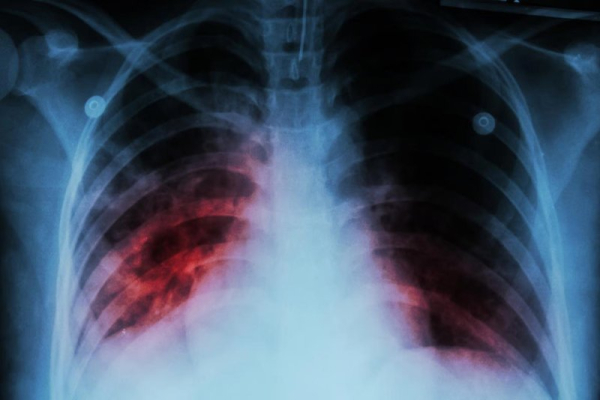

Tuberculosis is again the leading cause of deaths from infectious disease after COVID-19 displaced it briefly during the pandemic. Photo by Adobe Stock/HealthDay News

Tuberculosis is caused by airborne bacteria that mostly attacks the lungs. Roughly a quarter of the global population is estimated to have TB, but only about 5% to 10% of those develop symptoms, the WHO said.